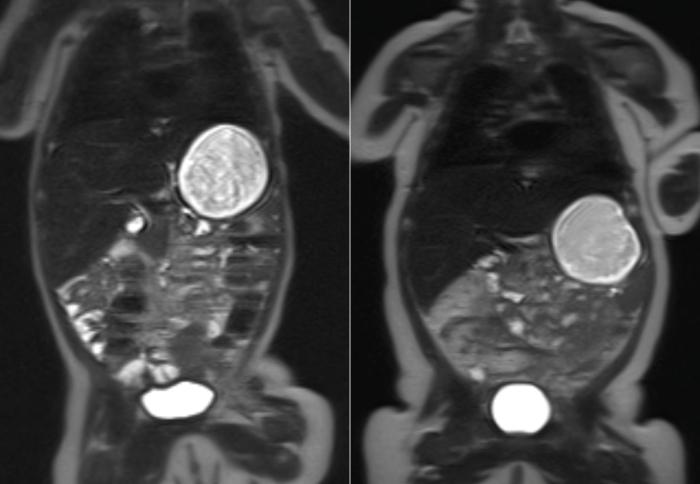

These are MRI scans of two babies at ten weeks old. The child on the left was born to a healthy mother, while the child on the right was born to a mother with gestational diabetes. The white area on the outside of the body is fat tissue. (The large white circle in the body is milk in the stomach)